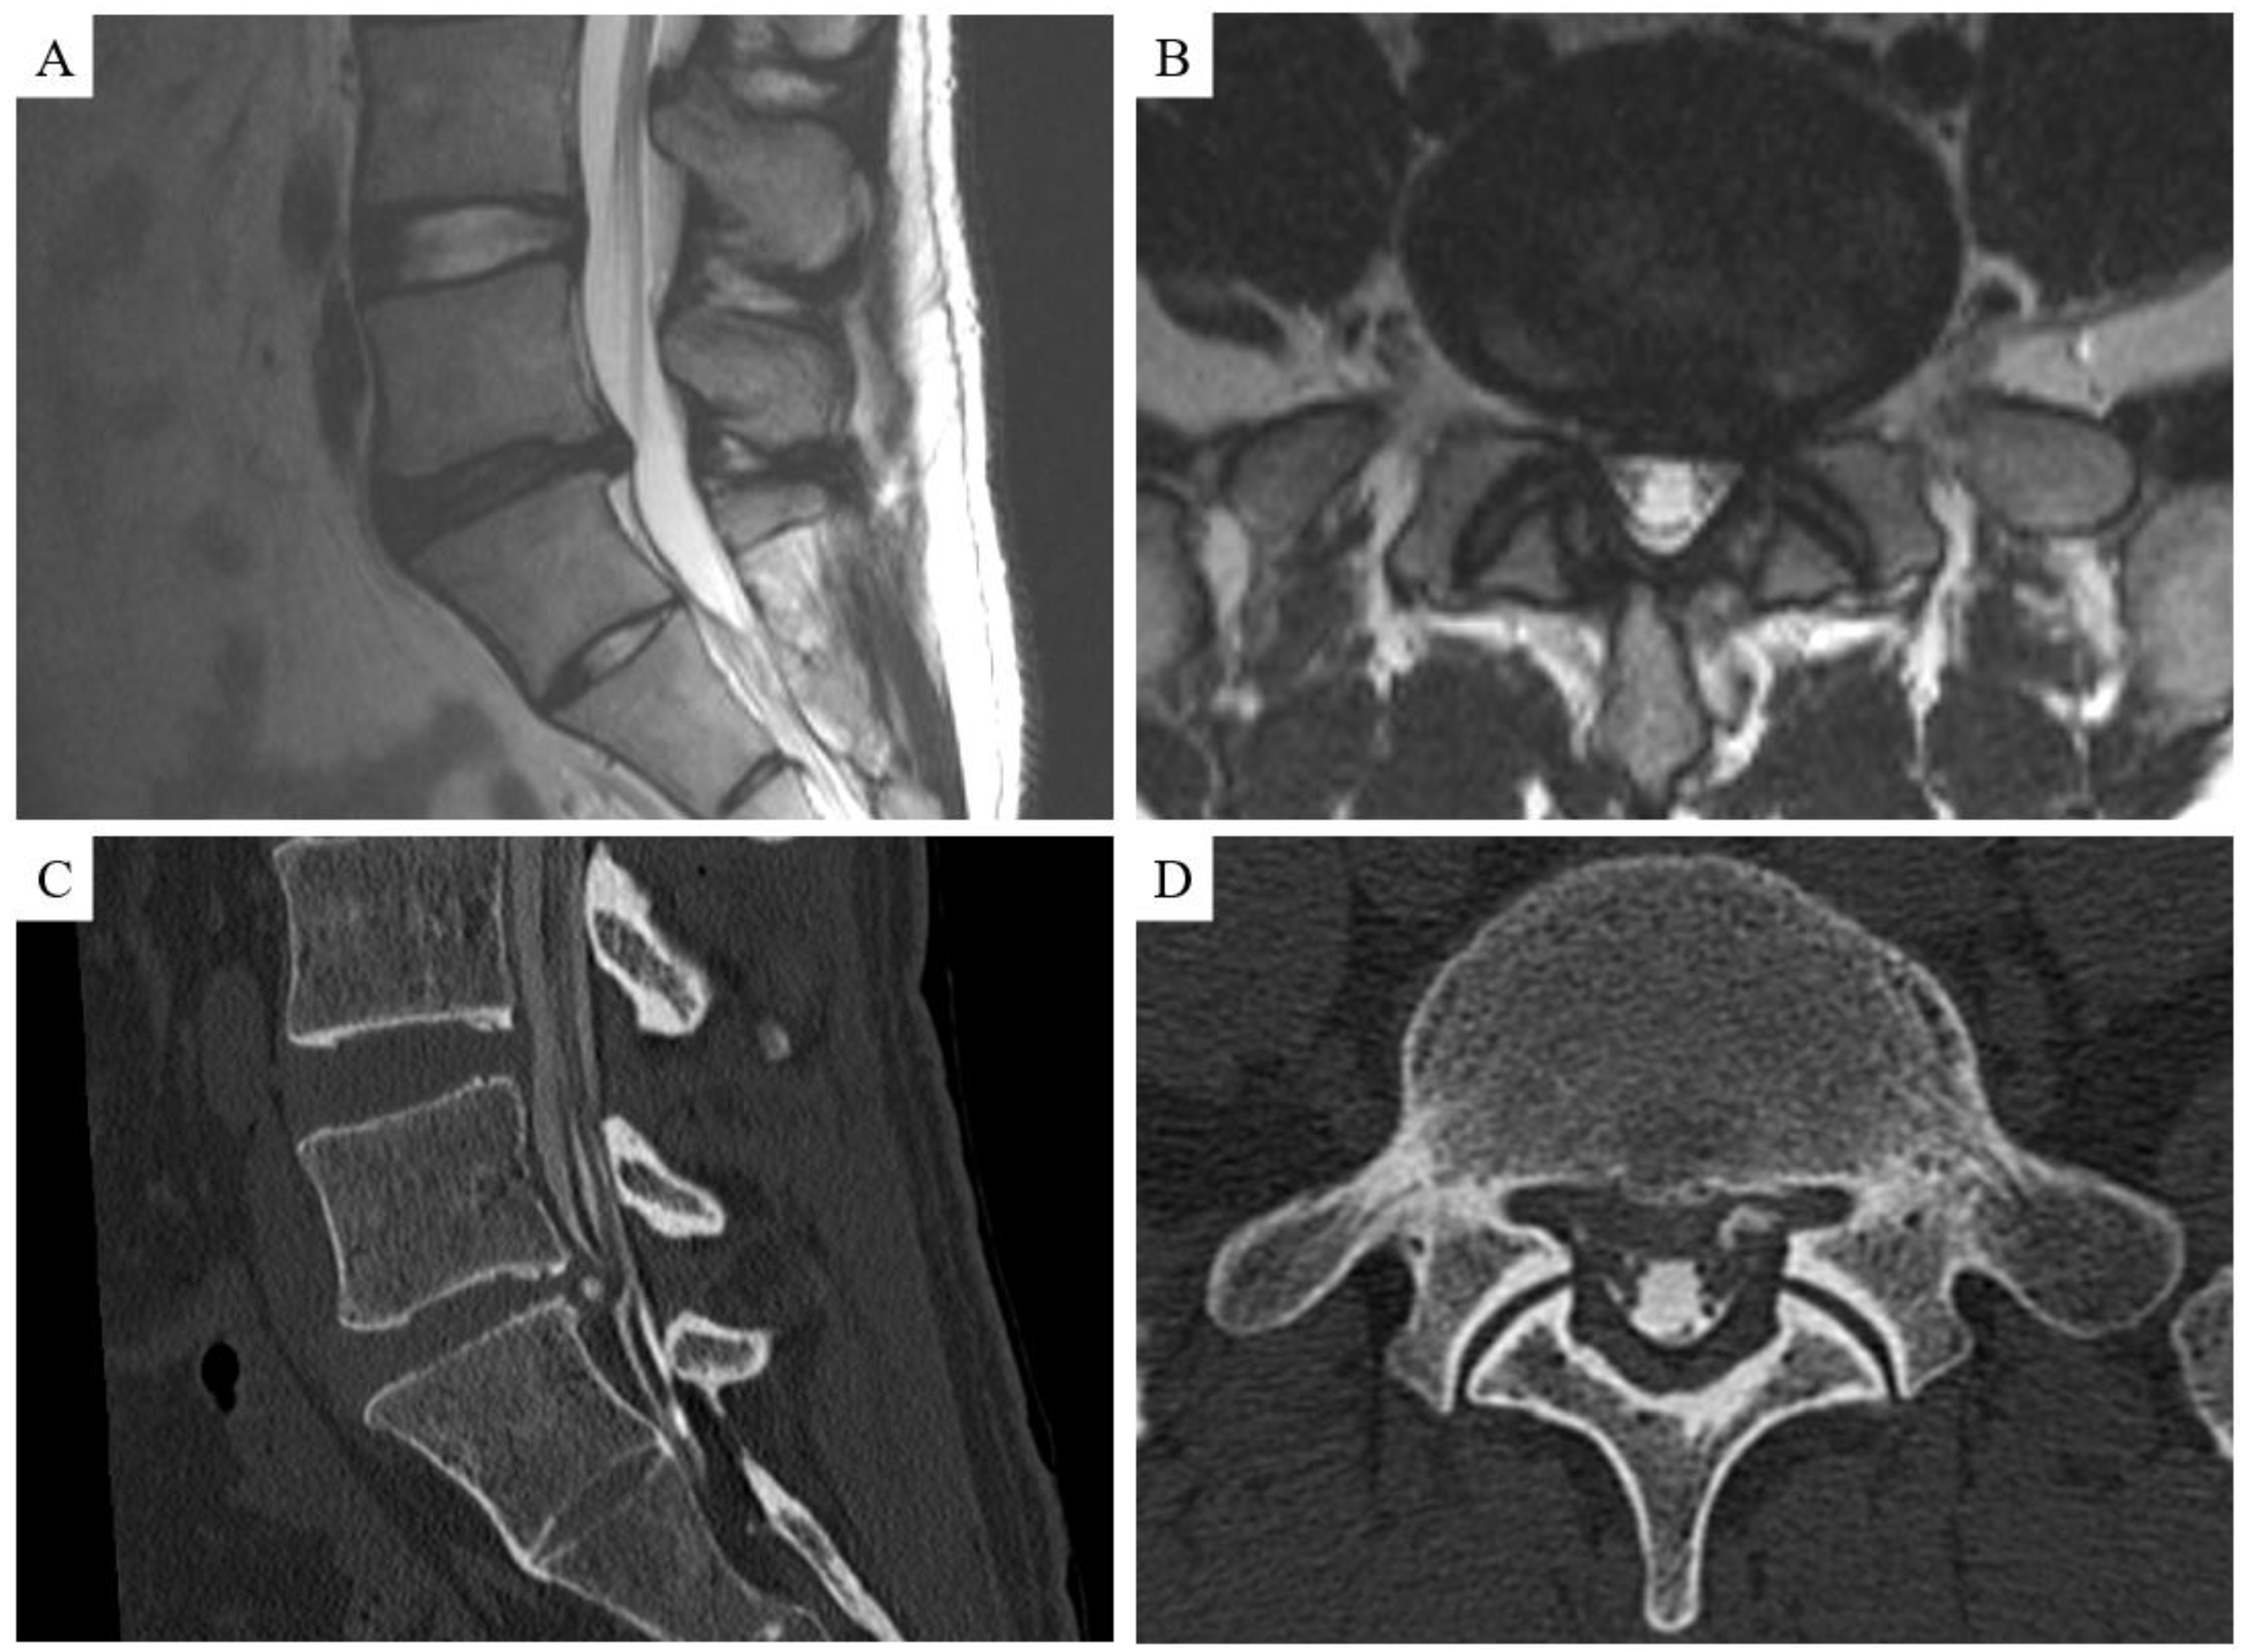

| Calcification or ossification | 9 (28.1%) | 1 (5.3%) | 8 (61.5%) | <0.001 |